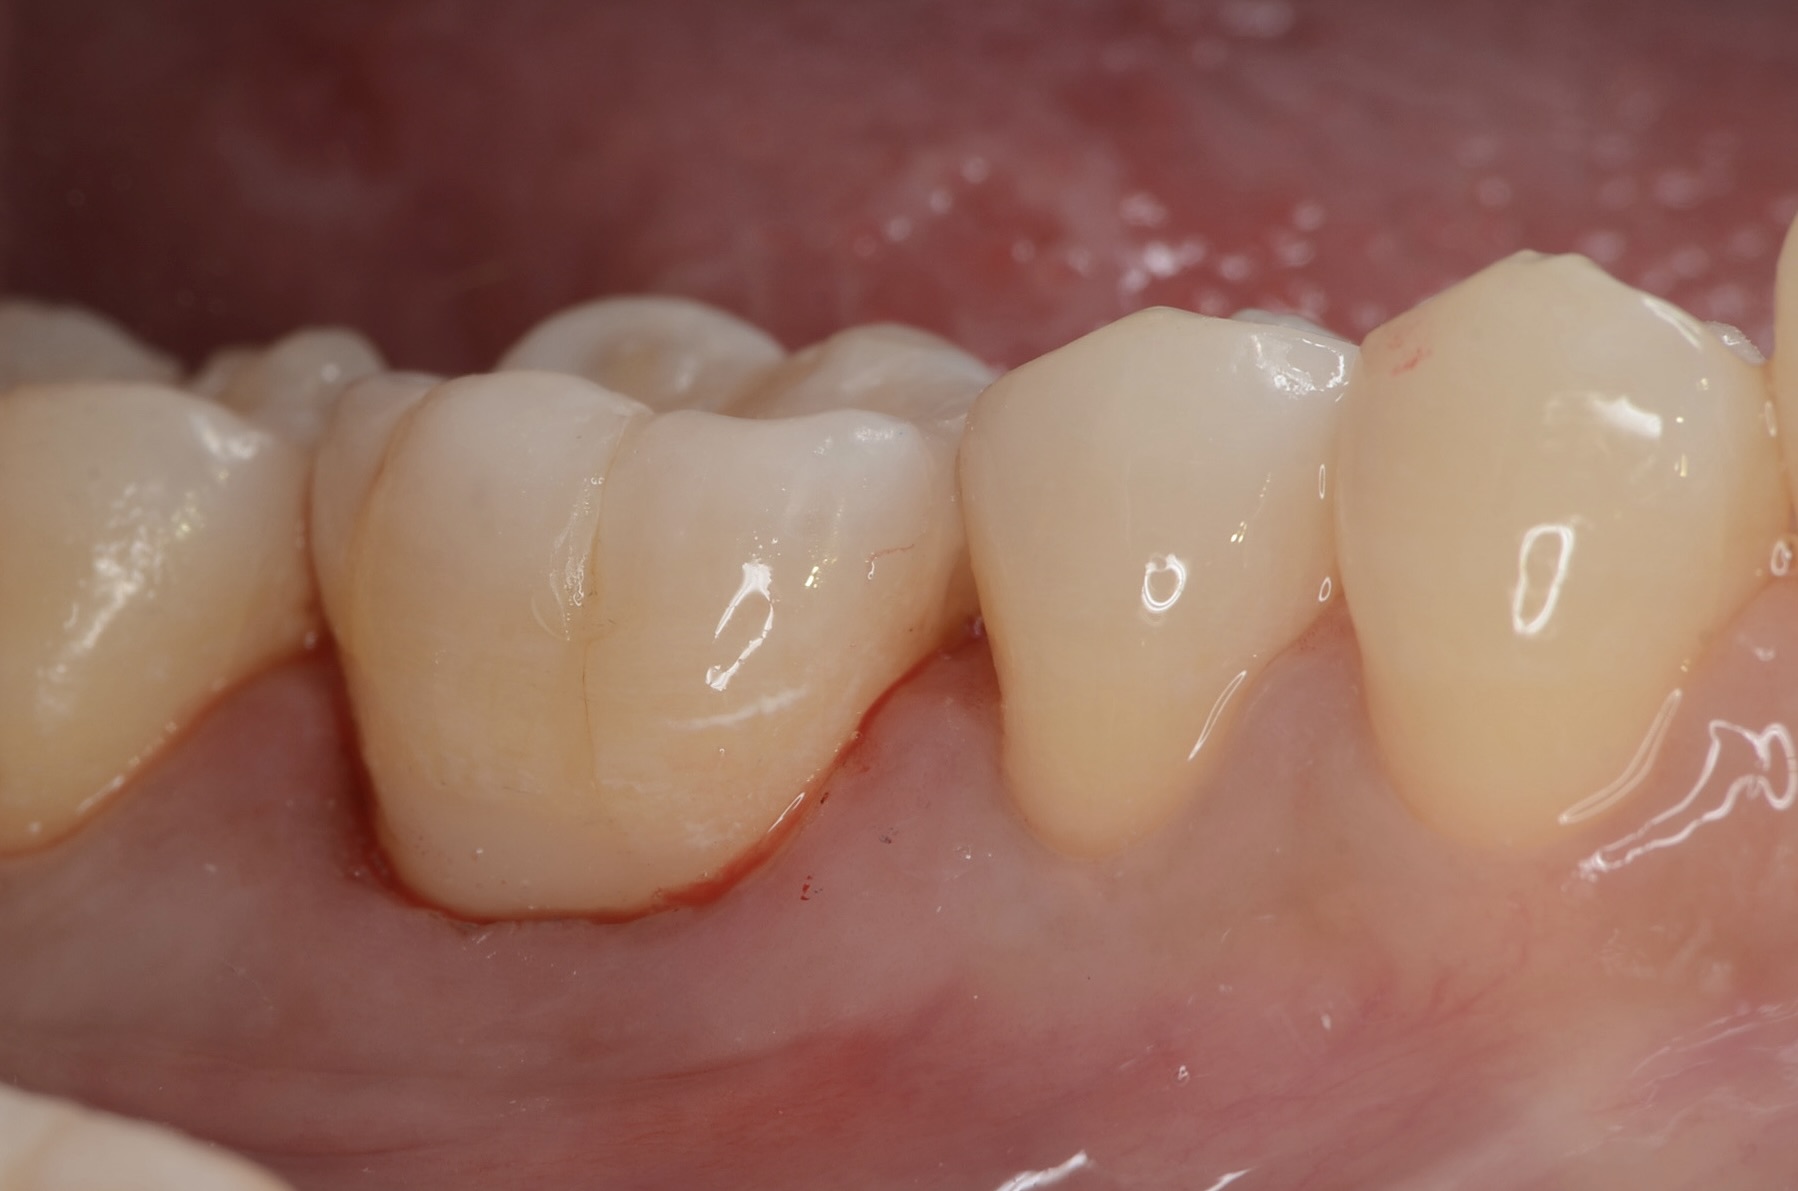

6番側方面観

歯と歯茎の境に古いレジン充填があります。その縁が黒ずみ虫歯になっています。 -